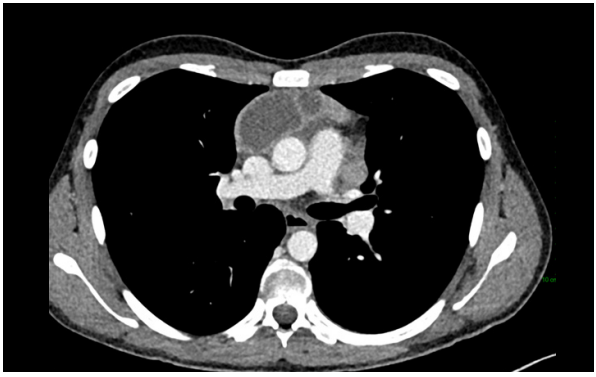

The patient underwent a CT scan the following day. A multilocular cystic mass was identified on CT in the mediastinum, accompanied by numerous enlarged lymph nodes located centrally in the chest.